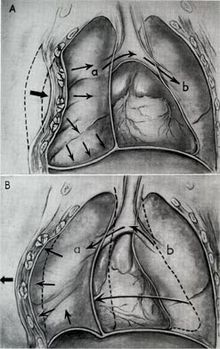

The term blunt thoracic trauma, or, more informally, blunt chest injury, encompasses a variety of injuries to the chest. Broadly, this also includes damage caused by direct blunt force (such as a fist or a bat in an assault), acceleration or deceleration (such as that from a rear-end automotive accident), shear force (a combination of acceleration and deceleration), compression (such as a heavy object falling on a person), and blasts (such as an explosion of some sort). Common signs and symptoms include something as simple as bruising, but occasionally as complicated as hypoxia, ventilation-perfusion mismatch, hypovolemia, and reduced cardiac output due to the way the thoracic organs may have been affected. Blunt thoracic trauma is not always visible from the outside and such internal injuries may not show signs or symptoms at the time the trauma initially occurs or even until hours after. A high degree of clinical suspicion may sometimes be required to identify such injuries, a CT scan may prove useful in such instances. Those experiencing more obvious complications from a blunt chest injury will likely undergo a focused assessment with sonography for trauma (FAST) which can reliably detect a significant amount of blood around the heart or in the lung by using a special machine that visualizes sound waves sent through the body. Only 10-15% of thoracic traumas require surgery, but they can have serious impacts on the heart, lungs, and great vessels.[13]

The most immediate life-threatening injuries that may occur include tension pneumothorax, open pneumothorax, hemothorax, flail chest, cardiac tamponade, and airway obstruction/rupture.[13]

The injuries may necessitate a procedure, with the most common being the insertion of an intercostal drain, more commonly referred to as a chest tube. This tube is typically placed because it helps restore a certain balance in pressures (usually due to misplaced air or surrounding blood) that are impeding the lungs ability to inflate and thus exchange vital gases that allow the body to function.[14] A less common procedure that may be employed is a pericardiocentesis which by removing blood surrounding the heart, permits the heart to regain some ability to appropriately pump blood.[15][16] In certain dire circumstances an emergent thoracotomy may be employed.[17]